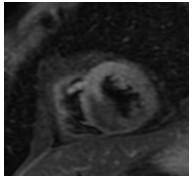

入院后签署患者知情同意告知书,查血常规、凝血谱、电解质、血生化、甲状腺功能、肿瘤标志物、C反应蛋白和脑钠肽均未见明显异常,心电图示窦性心律,顺钟向转位。连续心电遥控监护5 d未见明显室性心律失常。心脏超声和经食道心脏超声检查提示室间隔及左室下壁中段近后内侧乳头肌处可见一个偏高回声区,主要位于心肌内,浸润心肌全层,部分凸向左室腔,略见活动及变形,未累及二尖瓣和主动脉瓣,未见心腔流入道和流出道梗阻,未见明显心包积液。左心声学造影显示室间隔中下段偏强回声团块内未见明显血流信号,乏血供表现。心脏多层螺旋计算机断层扫描(CT)示室间隔内异常密度,测其CT值为-31.3 Hu,提示为脂肪组织密度,增强后病灶未见强化,诊断为脂肪来源肿瘤,脂肪瘤考虑(图 1~2)。心脏磁共振(CMRI)增强扫描示FIESTA序列显示后室间隔-左室下壁见一混杂高信号“小核桃”样大小肿物,T2WI(图 3)上为高信号,Triple IR序列(图 4)上病灶全部为低信号,提示为纯脂肪成分,病变周围可见低信号环,提示为化学位移伪影,病变质地较软,边界尚清楚,电影序列可见病灶柔软摆动,并随心动周期形态改变,局部突入左心室,舒张末期测量大小约25 mm×19 mm×36 mm,灌注序列见灌注确实,延迟增强未见强化,拟诊为心脏脂肪瘤(图 5)。SPECT心肌静息灌注显像见室间隔和左室下壁局部心肌血流灌注减低。18F-FDG PET-CT显像提示室间隔-左室下壁心肌内病变糖代谢减低,考虑为脂肪源性病变,全身未见局部异常密度增高。

| 图 2 心脏增强CT图 |

当发现存在心脏肿瘤时,首先需要明确其性质,尤其是良恶性。CT和磁共振对脂肪瘤的识别具有高度特异性[12-13],本患者CT检查示室间隔脂肪组织均匀低密度影。MR清晰显示肿瘤边界,T1W1呈强信号,T2W1呈稍强信号,脂肪组织序列呈弱信号,钆增强后也未见明显强化,对映证脂肪瘤均有较大价值。患者肿瘤的CT值同皮下脂肪组织,同时结合心超等其他影像学依据可排除黏液样变、血管组织、肌肉组织、纤维组织和错构瘤等其他组织来源,因此可临床确诊为脂肪来源的肿瘤。肿瘤形态、血供是否丰富和代谢是否活跃是鉴别脂肪瘤和脂肪肉瘤的重要依据。超声、CT和磁共振均提示肿瘤为单个,与周围组织边界清楚。患者接受了超声左心声学造影和核素心肌静息灌注显像检查,均提示肿瘤血供明显不丰富。18F-FDG PET-CT检查显示肿瘤放射性摄取呈稀疏缺损区,提示葡萄糖代谢减低,符合良性肿瘤表现,同时也未见全身其余部位有高糖代谢病灶,因此临床诊断良性脂肪瘤成立。2011年AECVP/SCVP心内膜心肌活检共识声明认为对左心系统肿瘤无需进一步进行心肌活检[7]。